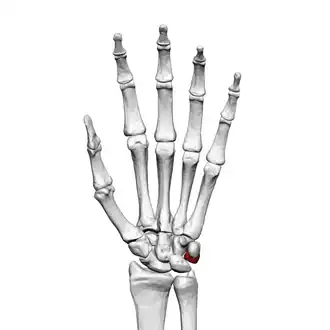

![]() Left hand anterior view (palmar view). Triquetral bone shown in red. | |

The triquetral bone (/traɪˈkwɛtrəl, -ˈkwiː-/; also called triquetrum, pyramidal, three-faced, and formerly cuneiform bone) is located in the wrist on the medial side of the proximal row of the carpus between the lunate and pisiform bones. It is on the ulnar side of the hand, but does not directly articulate with the ulna. Instead, it is connected to and articulates with the ulna through the Triangular fibrocartilage disc[1] and ligament, which forms part of the ulnocarpal joint capsule.[2] It connects with the pisiform, hamate, and lunate bones. It is the 2nd most commonly fractured carpal bone.

The triquetral is one of the eight carpal bones of the hand. It is a three-faced bone found within the proximal row of carpal bones. Situated beneath the pisiform, it is one of the carpal bones that form the carpal arch, within which lies the carpal tunnel. [3]: 708

The triquetral bone may be distinguished by its pyramidal shape, and by an oval isolated facet for articulation with the pisiform bone. It is situated at the upper and ulnar side of the carpus. To facilitate its palpation in an exam, the hand must be radially deviated so that the triquetrium moves out from under the ulnar styloid process. The triquetrum may be difficult to find, since it also lies under the pisiform.